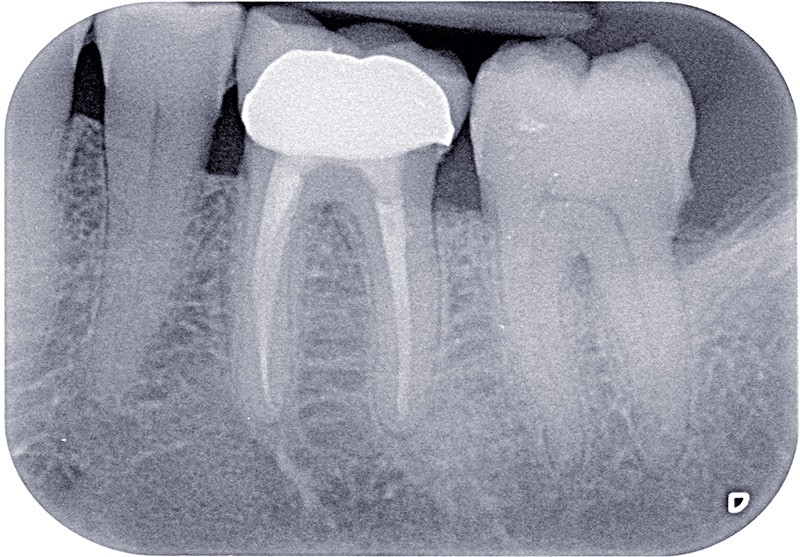

Dans ces situations, le praticien est conduit à dépulper et à restaurer les dents traitées endodontiquement. Les traitements doivent alors s’inscrire dans le concept du continuum endo-restaurateur qui a été défini comme étant « le processus spatio-temporel sans interruption ni rupture qui débute par l’accès à l’endodonte et s’achève avec la mise en place de la restauration prothétique d’usage » (1). Il existe bien une continuité, du traitement endodontique à la restauration fonctionnelle d’usage qui conditionne le pronostic et les résultats du traitement à long terme (fig. 2).